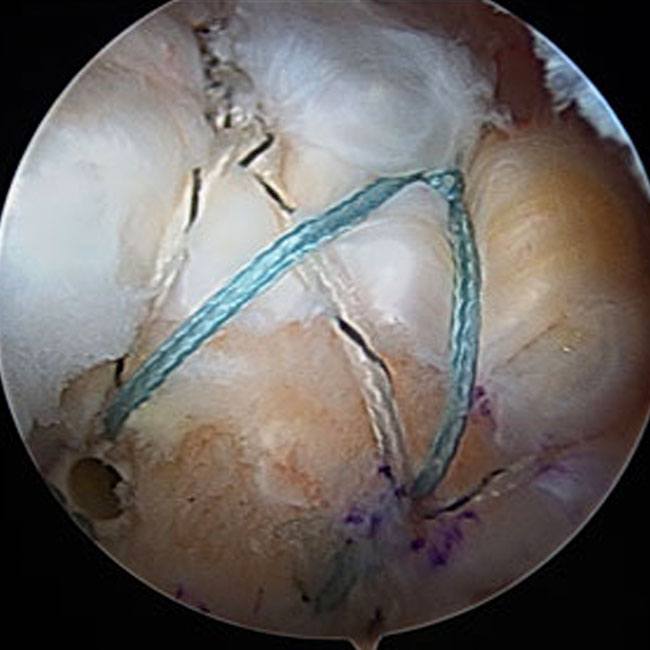

Surgery is performed arthroscopically in the outpatient setting (same day surgery). General or nerve block anesthesia is administered. Three to four small incisions (5 mm) are made in the shoulder to allow a camera and specialized instruments into the shoulder. Inflamed bursa and bone spurs are removed arthroscopically, creating space for the rotator cuff muscles and eliminating impingement. Suture anchors are utilized for the repair. Suture anchors are small metal or bioabsorbable screws that have two sutures each attached to them. After mobilizing the tendon so that it can be anatomically repaired, suture anchors are inserted in bone. The sutures from the anchors are passed through the tendon and used to repair the rotator cuff securely to the bone arthroscopically. Sometimes, if tissue quality and tear configuration allows, a double row of suture anchors is used to add strength to the repair. Below are some images that illustrate rotator cuff repair.

Figure 3A and 3B: Metal and Biocompatible suture anchors used in rotator cuff repair. These devices are inserted into bone to act as a fixation point for the rotator cuff to be reattached to bone. Figure 3C: shows a large crescent shaped rotator cuff tear. Figure 3D: The rotator cuff is repaired to bone arthroscopically to bone with a double row configuration.

Figure 3D

Figure 4G Completed double row repair